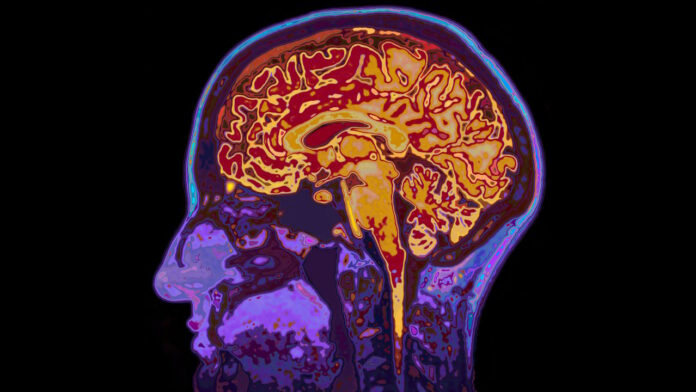

Une étude récente menée par l’université Harvard et publiée le 6 août 2025 dans la revue Nature révèle qu’une concentration anormalement faible de lithium dans le cerveau pourrait jouer un rôle clé dans le développement de la maladie d’Alzheimer. Les chercheurs ont constaté que ce déficit est particulièrement marqué chez les patients atteints, le lithium étant piégé dans les plaques amyloïdes responsables de la dégénérescence des neurones. Des expérimentations sur des souris privées de ce métal ont montré qu’un rééquilibrage permettait de réduire les lésions cérébrales et d’améliorer la mémoire, même lorsque la maladie était déjà installée.